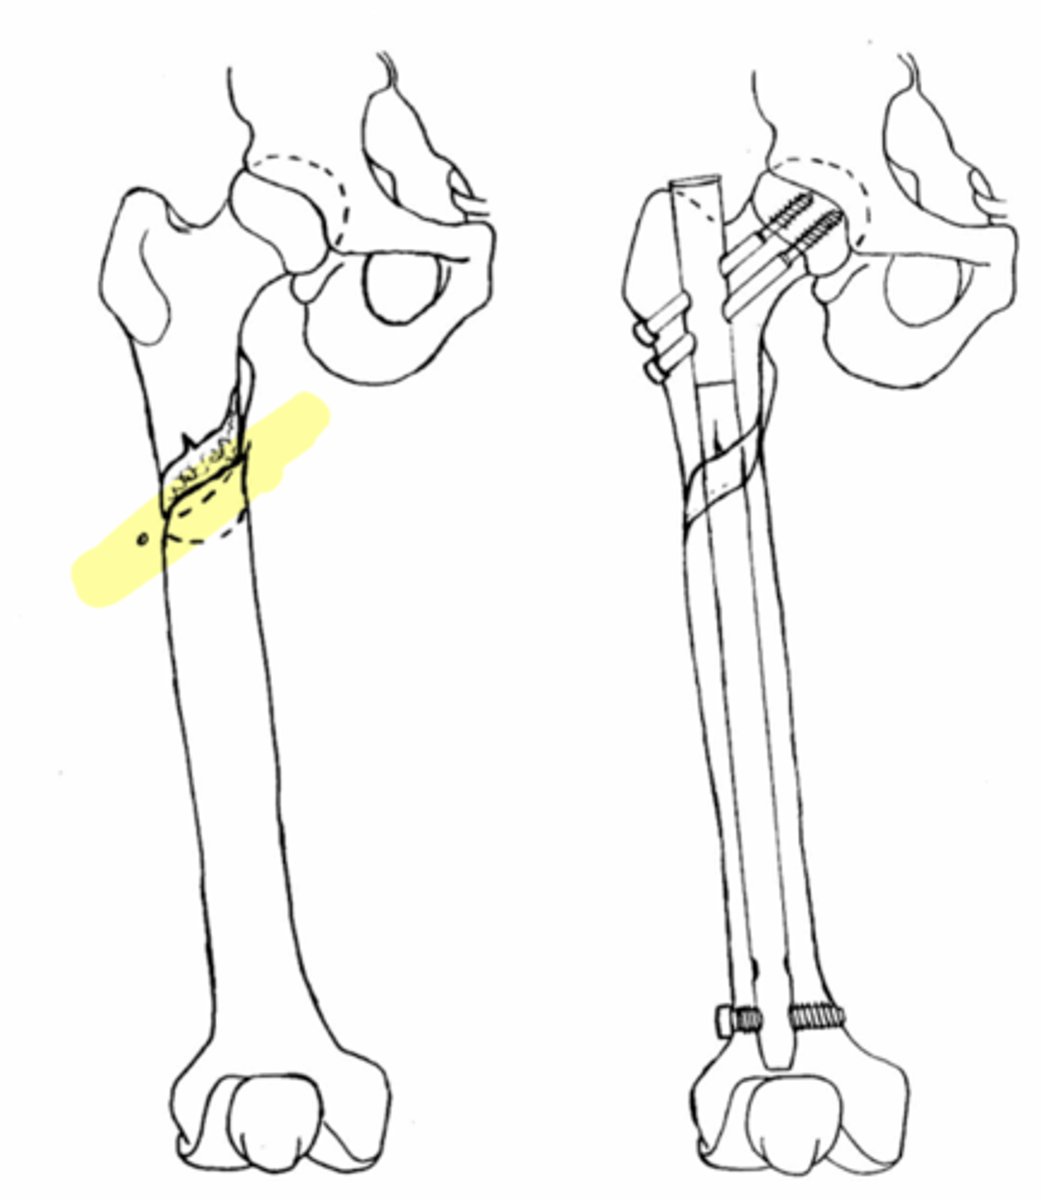

subtrochanteric fx

subtrochanteric fx